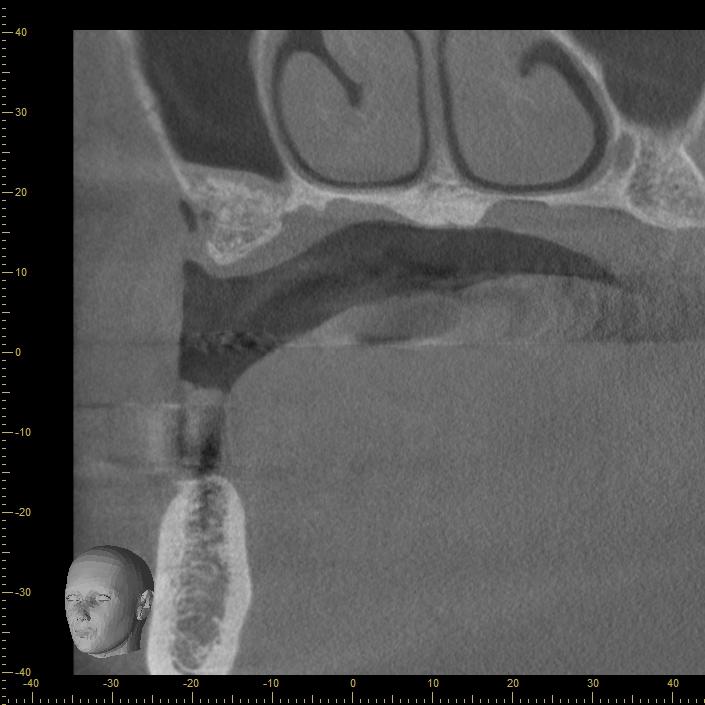

CT

インプラントは、骨の部分に埋め込む必要があります。骨には血管や神経が通っているため、埋め込む際はこれらを傷つけないように注意しなければなりません。

どこに血管や神経が通っているのかを把握するのに役立つのがCTです。CT検査を行うことで、お口の中を360度しっかり撮影できるので、安全な治療が行えるようになります